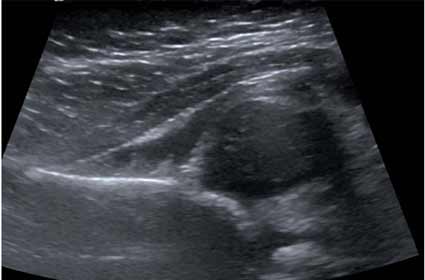

Ultrasonido mostrando cadera dislocada—cabeza de fémur fuera de alineamiento con la cuenca de la cadera.

Nota: Las imágenes se muestra para fines ilustrativos. No trate de sacar conclusiones comparando esta imagen con otras en el sitio. Solamente los radiólogos calificados deben interpretar las imágenes.